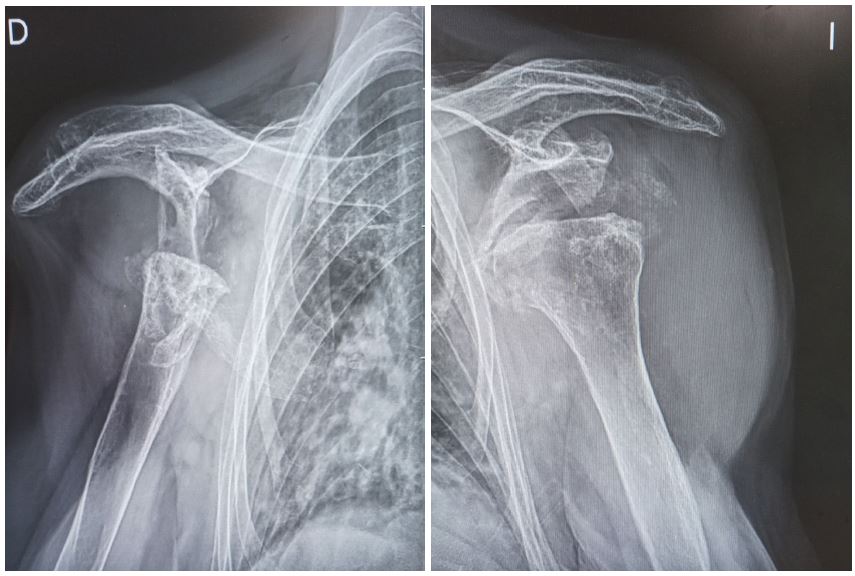

After this, a simple X-ray of both shoulders is requested (Figure 1).

Figure 1: Alteration of the morphology of both glenohumeral joints, with disappearance of the right humeral head (D), and deformity of the left humeral head with flattening and irregularity of its cortex at the anterosuperior level, with the existence of geodes and subchondral sclerosis (I)